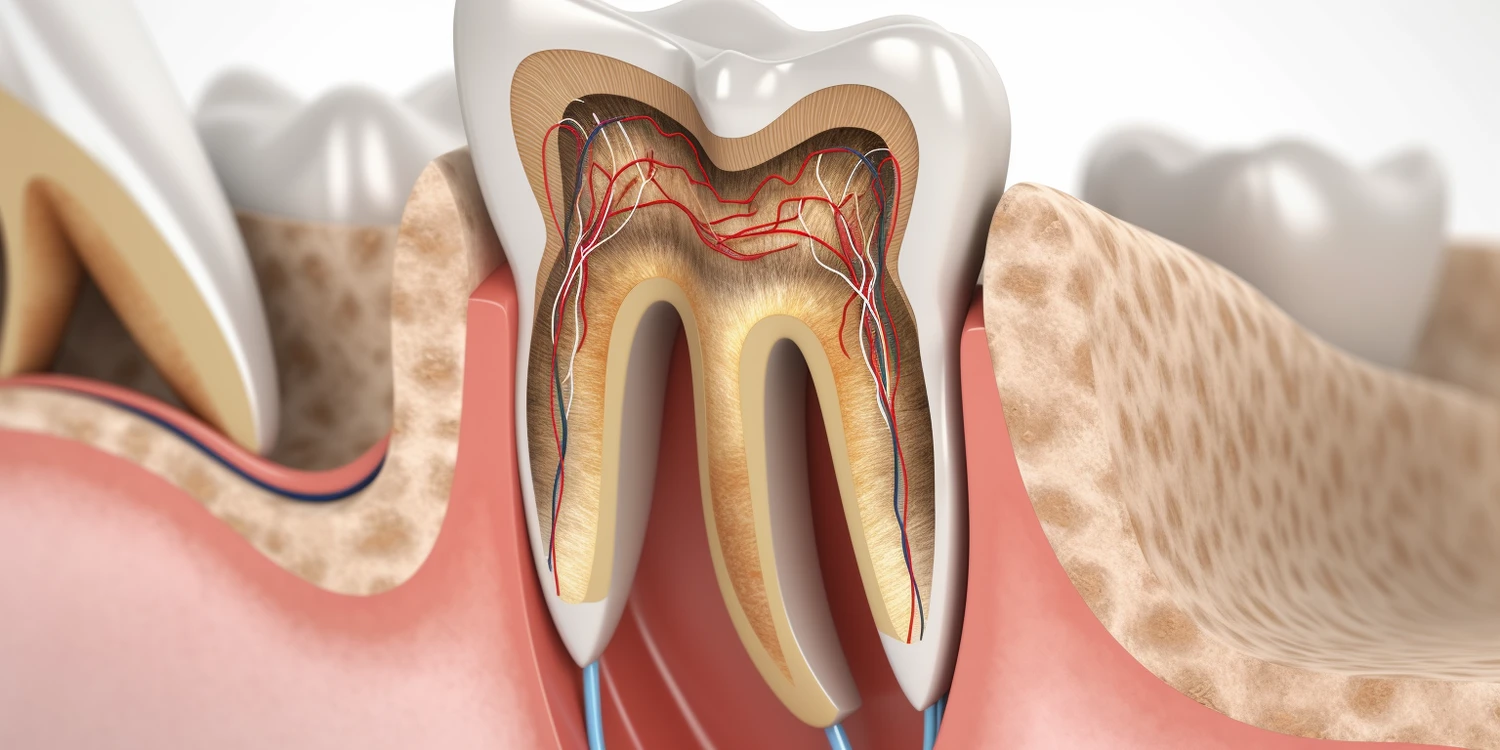

Ból zęba to jeden z najczęstszych powodów wizyt u stomatologa i w wielu przypadkach może prowadzić do potrzeby uzyskania zwolnienia lekarskiego. Jeśli ból jest intensywny i uniemożliwia normalne funkcjonowanie w pracy, stomatolog może rozważyć wystawienie L4. Warto jednak pamiętać, że samo zgłoszenie bólu zęba nie zawsze automatycznie skutkuje otrzymaniem zwolnienia. Lekarz musi przeprowadzić dokładną diagnostykę oraz ocenić stan zdrowia pacjenta. W przypadku poważnych schorzeń, takich jak ropień czy zapalenie miazgi zębowej, które wymagają interwencji chirurgicznej lub długotrwałego leczenia, stomatolog ma pełne prawo do wystawienia L4. Pacjenci powinni być świadomi, że każdy przypadek jest indywidualny i decyzja o wystawieniu zwolnienia zależy od oceny lekarza oraz specyfiki danego schorzenia.

Choroby przyzębia to poważne schorzenia jamy ustnej, które mogą prowadzić do wielu komplikacji zdrowotnych. Pacjenci cierpiący na te dolegliwości często odczuwają silny ból oraz dyskomfort związany z zapaleniem dziąseł i tkanki otaczającej zęby. W takich przypadkach stomatolog ma możliwość wystawienia zwolnienia lekarskiego dla pacjenta. Decyzja ta opiera się na ocenie stanu zdrowia oraz wpływie choroby na zdolność do pracy. Jeśli choroba przyzębia wymaga intensywnego leczenia lub zabiegów chirurgicznych, które mogą wpłynąć na codzienne funkcjonowanie pacjenta, lekarz dentysta ma prawo wystawić L4 na czas potrzebny do regeneracji i leczenia. Ważne jest jednak, aby pacjent regularnie uczęszczał na wizyty kontrolne oraz stosował się do zaleceń lekarza dotyczących higieny jamy ustnej i leczenia choroby przyzębia.

Infekcje jamy ustnej mogą prowadzić do poważnych problemów zdrowotnych i znacznego dyskomfortu. W przypadku infekcji, takich jak zapalenie dziąseł czy ropień zębowy, pacjenci często odczuwają silny ból oraz mają trudności z jedzeniem i mówieniem. W takich sytuacjach stomatolog może rozważyć wystawienie zwolnienia lekarskiego. Jeśli infekcja jest na tyle poważna, że wymaga intensywnego leczenia lub hospitalizacji, lekarz dentysta ma prawo do wystawienia L4 na czas potrzebny do leczenia i regeneracji. Kluczowe jest jednak, aby pacjent zgłosił wszystkie objawy oraz ich nasilenie podczas wizyty u stomatologa. Lekarz przeprowadzi odpowiednie badania i na podstawie wyników podejmie decyzję o konieczności wystawienia zwolnienia lekarskiego.